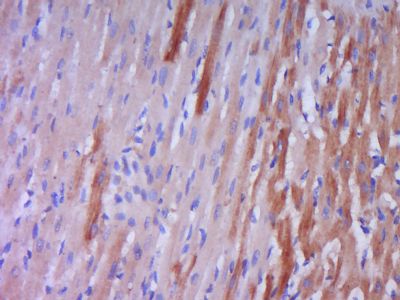

| 产品图片 | ![]() Sample: Liver (Mouse) Lysate at 40 ug Liver (Rat) Lysate at 40 ug Primary: Anti-Big endothelin-1 (bs-0188R) at 1/300 dilution Secondary: IRDye800CW Goat Anti-Rabbit IgG at 1/20000 dilution Predicted band size: 22 kD Observed band size: 22 kD ![]() Tissue/cell: Rat stomach tissue; 4% Paraformaldehyde-fixed and paraffin-embedded; Antigen retrieval: citrate buffer ( 0.01M, pH 6.0 ), Boiling bathing for 15min; Block endogenous peroxidase by 3% Hydrogen peroxide for 30min; Blocking buffer (normal goat serum,C-0005) at 37℃ for 20 min; Incubation: Anti- Big endothelin-1 Polyclonal Antibody, Unconjugated(bs-0118R) 1:200, overnight at 4°C, followed by conjugation to the secondary antibody(SP-0023) and DAB(C-0010) staining ![]() Tissue/cell: Rat lung tissue; 4% Paraformaldehyde-fixed and paraffin-embedded; Antigen retrieval: citrate buffer ( 0.01M, pH 6.0 ), Boiling bathing for 15min; Block endogenous peroxidase by 3% Hydrogen peroxide for 30min; Blocking buffer (normal goat serum,C-0005) at 37℃ for 20 min; Incubation: Anti- Big endothelin-1 Polyclonal Antibody, Unconjugated(bs-0118R) 1:200, overnight at 4°C, followed by conjugation to the secondary antibody(SP-0023) and DAB(C-0010) staining ![]() Paraformaldehyde-fixed, paraffin embedded (Rat heart); Antigen retrieval by boiling in sodium citrate buffer (pH6.0) for 15min; Block endogenous peroxidase by 3% hydrogen peroxide for 20 minutes; Blocking buffer (normal goat serum) at 37°C for 30min; Antibody incubation with (Big endothelin-1) Polyclonal Antibody, Unconjugated (bs-0188R) at 1:400 overnight at 4°C, followed by operating according to SP Kit(Rabbit) (sp-0023) instructionsand DAB staining. |